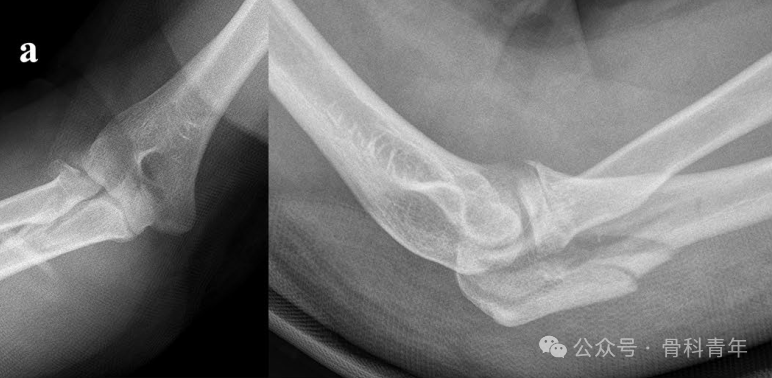

病例3:后孟氏骨折,桡骨头骨折采用2枚可吸收螺钉固定。